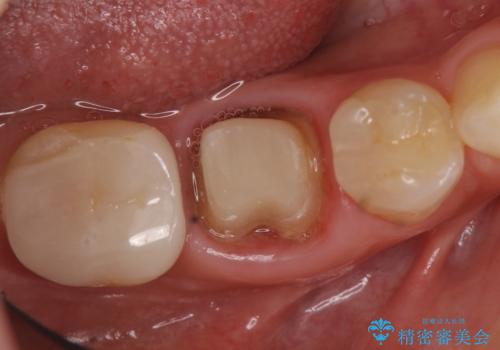

- たまに疼くことがあると他院を受診したところ抜歯を勧められたが、歯を残せないものかと当院にいらっしゃった方の症例です。

診査の結果抜歯の必要性はなさそうだったため再根管治療を行い、その後オールセラミッククラウンによる補綴を行いました。